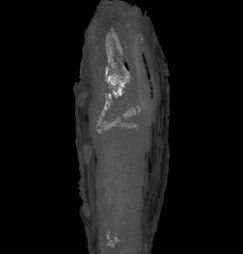

(NEWSER) – A tiny coffin believed for a century to be holding the organs of some ancient Egyptian or other actually contains what is likely the youngest mummy ever discovered, Discovery reports. Archaeologists dug up the 17-inch coffin in Giza, Egypt, in 1907, and it was handed over to the Fitzwilliam Museum in Britain. The coffin contained something wrapped in bandages and covered in black resin. According to the Washington Post, X-rays of the bundle were no help, and the museum went on believing it to be mummified organs removed during an embalming. That ended with an announcement Wednesday: The bundle is actually a fetus, believed to have been miscarried between 16 and 18 weeks gestation, mummified more than 2,500 years ago.

The Fitzwilliam Museum made the discovery after having Cambridge University's department of zoology perform a CT scan on the coffin for an upcoming exhibition. The scan showed a remarkable amount of preservation and detail, including all of the fetus's digits. The museum states the mummy was clearly the result of an important burial due to its arms being crossed over its chest and the elaborate carvings on the coffin. “This groundbreaking find educates us further still in our conception of just how precious the unborn child was in ancient Egyptian society,” the Guardian quotes the museum's head of conservation as saying. “The care taken in the preparation of this burial clearly demonstrates the value placed on life even in the first weeks of its inception.”